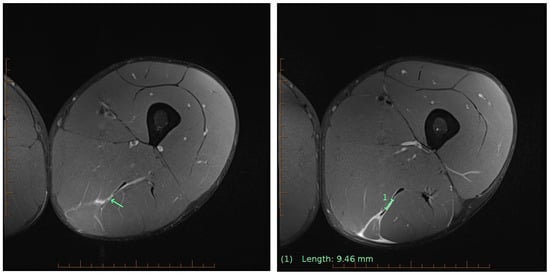

This case report describes the acceleration of an Olympic decathlete’s return to competition induced via high-frequency Blood Flow Restriction (BFR) training. BFR has gained popularity as an innovative rehabilitation method for promoting muscle repair and adaptation through anabolic and regenerative pathways when high mechanical loading is not possible. A 26-year-old elite decathlete with nine years of international experience sustained a Grade 2b strain of the semimembranosus and semitendinosus (a 9 mm central tendon tear) during a hurdle sprint. The injury was confirmed via MRI two days post-injury. Grade 2b hamstring injuries with intramuscular tendon involvement commonly require up to 4 weeks of rehabilitation before full training can be resumed. With the athlete due to complete in an Olympic Games competition 17 days post-injury, an intensive BFR-assisted rehabilitation program was initiated. Over 12 consecutive days, the athlete completed 3–6 BFR sessions per day (20–30 min each) at 50% limb occlusion pressure, along with physiotherapy and pain-limited functional testing. BFR was applied passively for recovery, during conditioning, and in low-load strength sessions. By day 12, sprint velocity reached 95% maximum, and the athlete successfully completed the decathlon, with no adverse effects or reinjury. This case illustrates how high-frequency BFR-assisted rehabilitation may facilitate accelerated recovery from a hamstring injury, enabling an effective return to elite competition within condensed timelines.